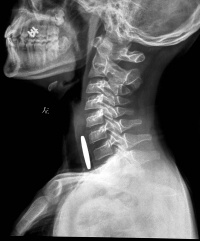

食管放射检查

2、上消化道钡餐X线检查:注意有无胃-食管反流、食管裂孔疝或食管狭窄,并了解胃和十二指肠情况。